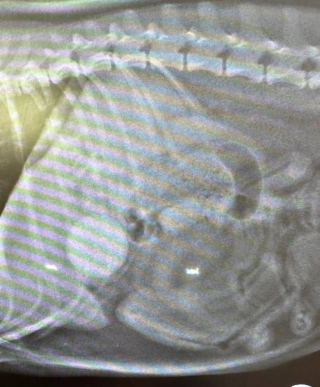

Le lendemain de leur balade à la plage, Pepper se sentait mal. Carol l’a alors conduite au cabinet vétérinaire Clifton Lodge Vets, où on lui a administré une injection, mais, 24 heures plus tard, son état s’est aggravé, comme elle l’expliquait au Teesside News. Alarmée par la léthargie de sa chienne qui s’était aussi mise à vomir, elle l’a ramenée en urgence au cabinet. Zoe Dykes, la vétérinaire, a aussitôt recommandé une analyse sanguine et une radiographie. Sur celle-ci, un objet était clairement visible et Carol ne s’attendait pas à ce qui a été découvert…

La balle avec laquelle Pepper avait joué était logée dans son estomac.